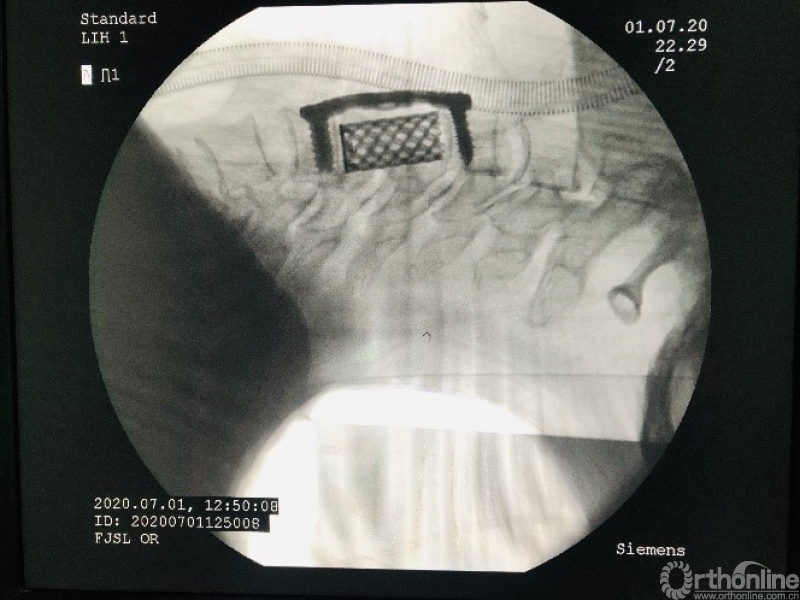

手术方案分析:存在脊髓压迫,为生长于脊髓腹侧硬膜发生的脊膜瘤,有硬膜基底。常规后路手术需要绕过脊髓切除位置固定的肿瘤,入路十分不合理。决定使用ACCF入路,切除硬膜下脊膜瘤。

术后分析:该例颈椎脊髓腹侧脊膜瘤,采用颈前路颈5椎体次全切除入路,避免了后路手术需要牵开脊髓与有重要功能神经根丝的危险操作,是比较合理的一种入路。

1. 次全切除椎体的开槽要足够寛,使用磨钻做骨壁的最后打磨,做到骨面不渗血,保持视野无血,保证显微操作清晰。